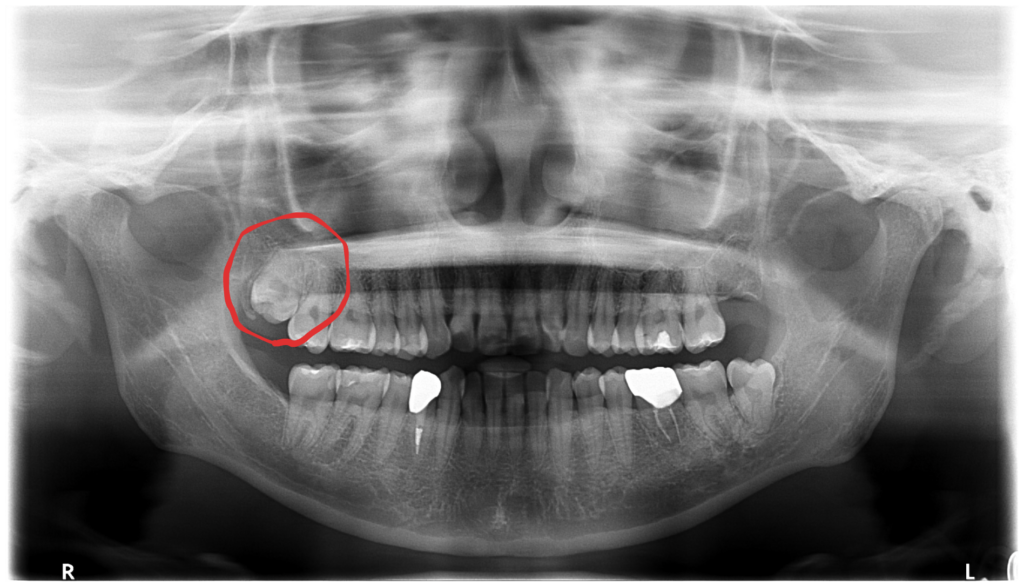

右上の親知らずが歯ぐきを刺激…当日抜歯で痛みを解決しました🦷【保険診療】

本日は「右上の歯ぐきが痛い」という主訴で来院された患者さんの治療をご紹介します。 診察してみると、右上の親知らず…